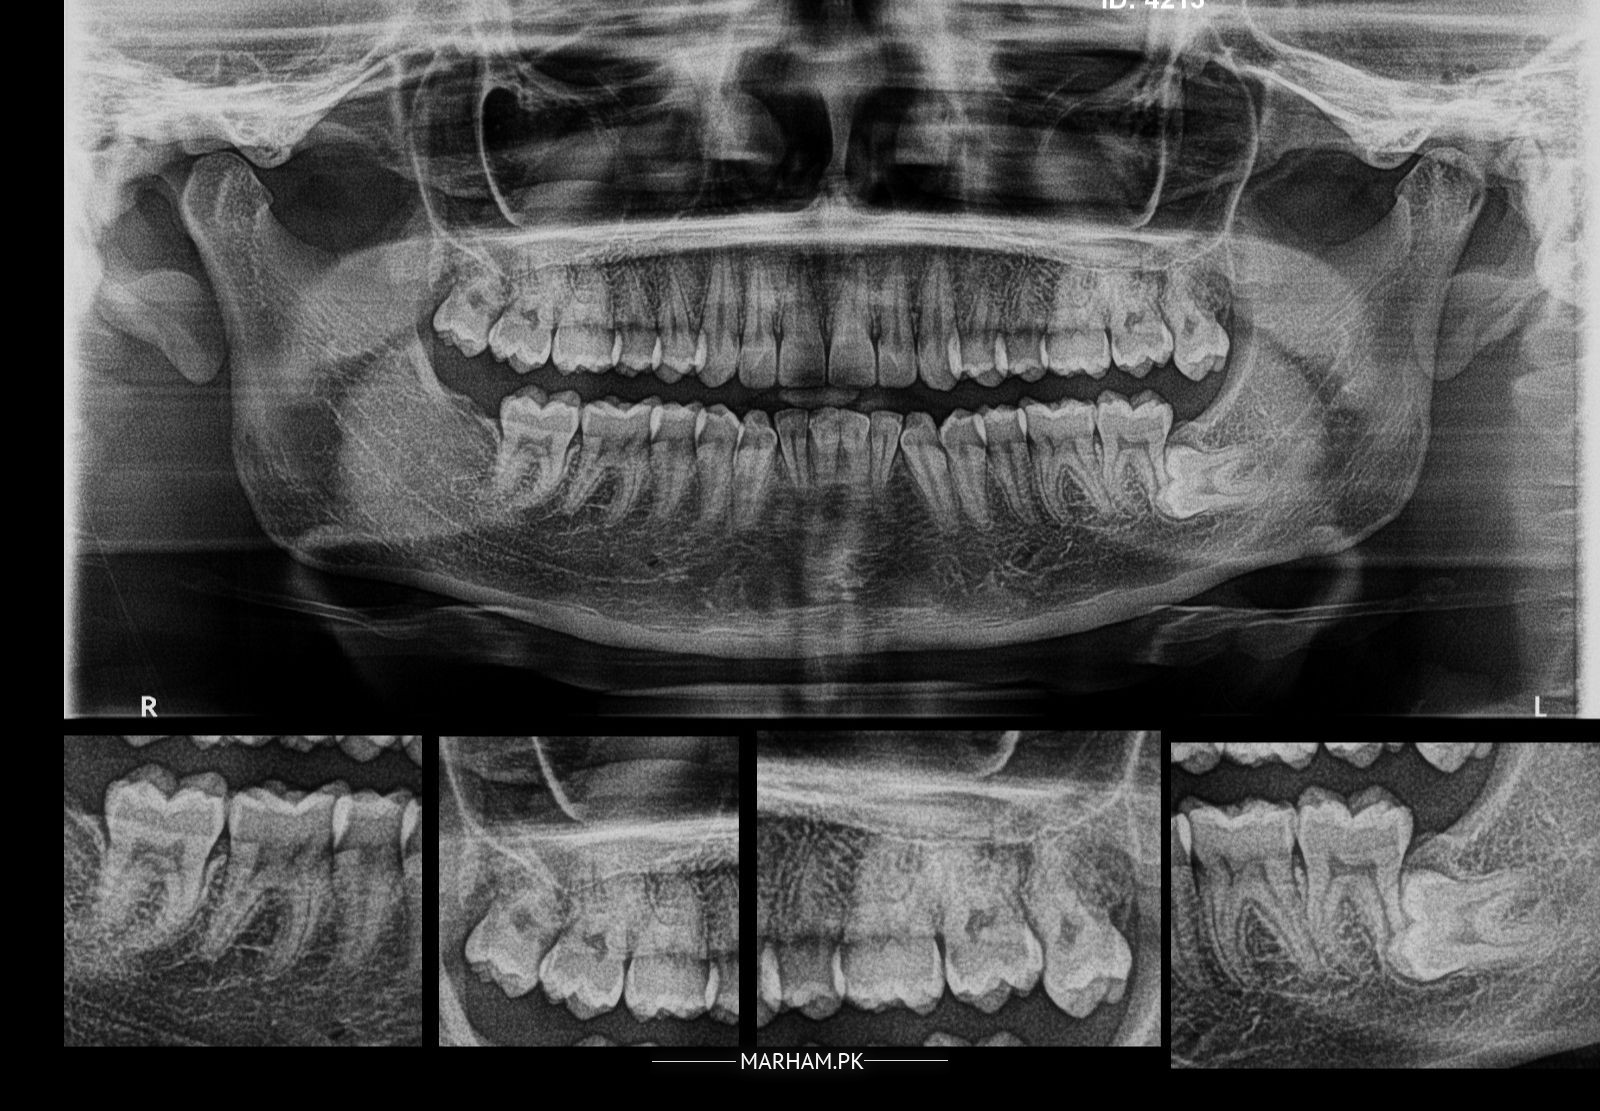

Assalamualaikum main ne opg x-ray krwaya hai, i want to ask k lower left side wisdom tooth to nikly gi but oper ki dono sides ki kesi hain, kia mjy wo bhi niklwani hon gi? kuch sal phly keay gaey x-ray ko dekhty hovy Dr ne btaya tha k oper ki bhi niklwani hon gi

Ws , definitely extractions dono ki hon gi, otherwise wo agay issue kren gay

Yes u have to extract all 3 of ur wisdom tooth

Walaikum us salam It is recommended to extract both sides upper wisdom teeth because when lower one is extracted upper ones after some time over erupt and can cause cheek bite or injury to gingiva and in some cases TMJ pain